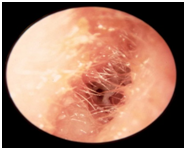

Ear canal infections- This is formally known as otitis externa and is an inflammation of the skin of the ear canal. This is characterized by swelling of the skin, redness and pain. This is sometimes accompanied by discharge. Often, the ear canal skin swells to the extent of completely obstructing the ear canal also causing hearing loss. (See picture 2)

Picture 2- otitis externa. Note the swollen ear canal skin. The ear drum cannot be seen. Drainage is also present. |